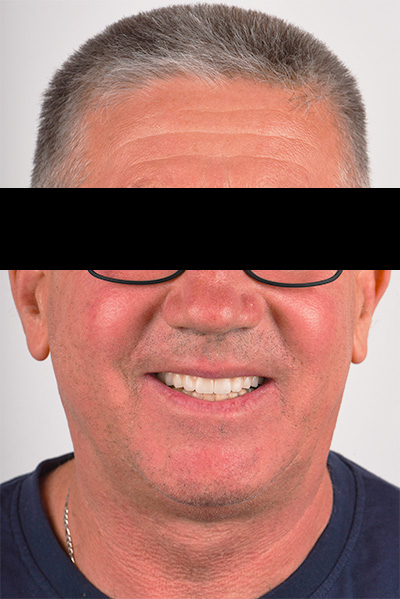

Fig. 09 : photo à 6 mois post-opératoire.

Fig. 09 : photo à 6 mois post-opératoire.

Fig. 10 : patient après post-opératoire.